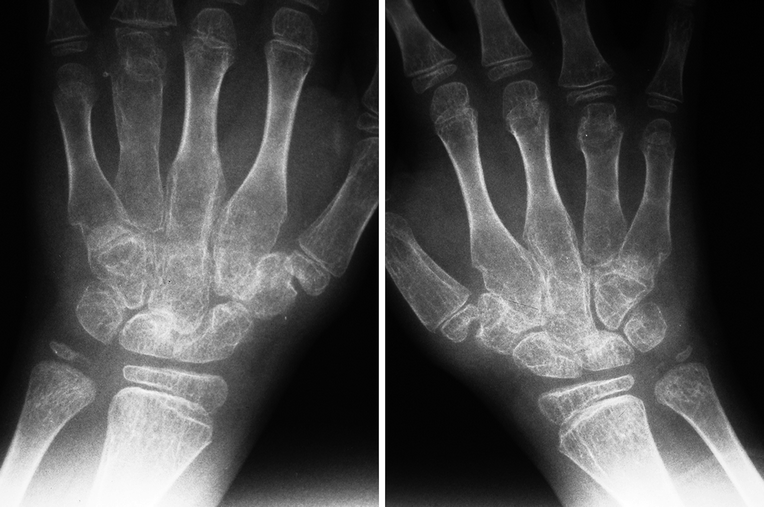

Juvenile Idiopathic Arthritis Radiology Key Juvenile Arthritis Eye Damage This eye inflammation is most common in children (more often girls) whose arthritis begins young (less than age 5), affects fewer than five. If left untreated, these problems can lead to vision loss. Inflammation of the uvea, the vascular layer of the eye, which is between the retina and the sclera. Some children with juvenile arthritis have eye problems, called. Juvenile Arthritis Eye Damage.